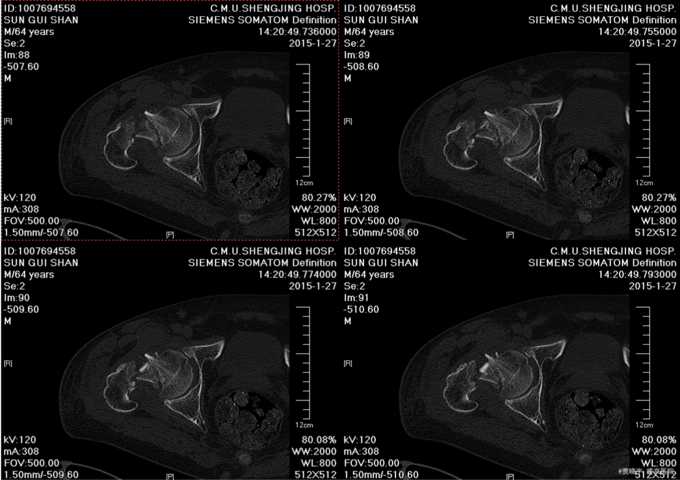

主诉:摔伤后右髋部疼痛肿胀活动受限5天。 现病史:患者男,75岁,患者家属述患者于2015-1-10日中午在自家走路时不慎摔倒,导致右大腿疼痛肿胀活动受限,无法站立行走,家人急送到当地医院,拍片检查,诊断为“右股骨颈骨折”,给予皮牵引治疗。现为求进一步治疗来我院,我科以“右股骨颈骨折”,收入院。患者自受伤以来,精神状态可,无发热,无呼吸困难,饮食睡眠正常,二便正常。

专科查体:患者平车入病房,右小腿胫骨牵引中,右下肢外展、外旋约45度,患肢缩短约1cm 右髋部疼痛,压痛(+),右下肢感觉未见异常,活动可,双侧足背动脉搏动可触及。